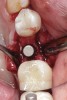

Fig 1. (Case 1) Tooth No. 19 manifested a buccal fistulous tract. Probing depth on the buccal was 8 mm.

Figure 1

Fig 11. An implant was placed in regenerated bone.

Figure 11